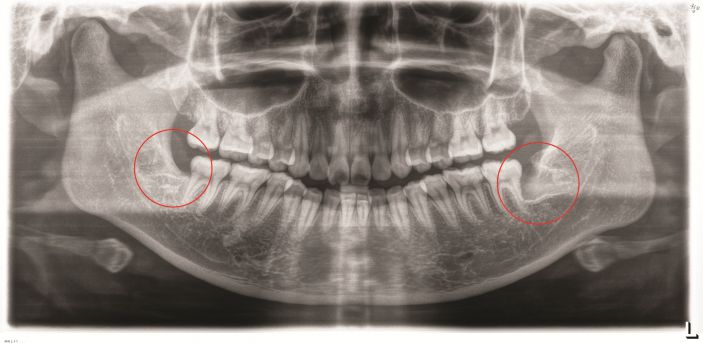

張主任講,微創拔智牙融合了多種先進的技術和理念,讓拔牙方式徹底告别盲目、暴力時代,具有這些優勢:1、個性化。術前通過CBCT明确患牙形态、埋伏深度及與下槽骨神經管、鄰牙的關系,分析骨阻力,設計、制定個性化的方案。2、創傷小。根據患牙特征,以減小創傷爲目的設計切口,采用超聲刀、切牙機等先進儀器設備,以小切口暴露牙冠,對患牙進行準确分割後經小切口逐一取出,告别傳統敲、鑿、劈、撬等一系列機械性操作,大幅度減少對正常組織的損傷。3、疼痛小、并發症少、恢複快。微創技術的應用,大幅減少智牙拔除的疼痛以及并發症,加快了術後的恢複。

△智牙拔除後。